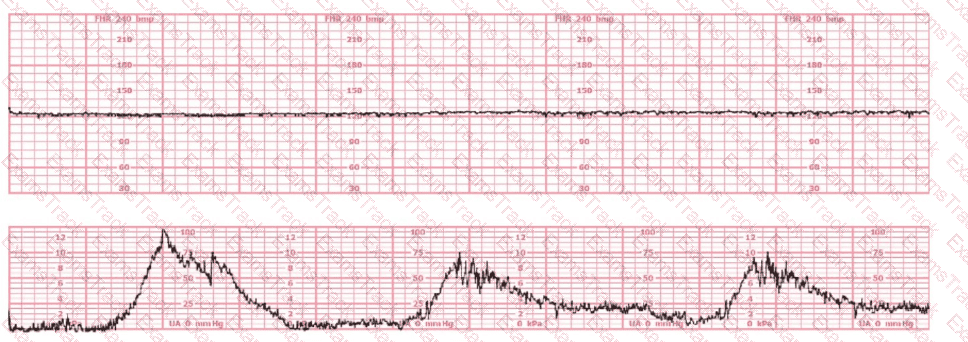

The tracing shown is from a woman at 28-weeks gestation in the post-anesthesia care unit (PACU) after an appendectomy. She is alert and awake. Based on this fetal heart rate pattern, the most appropriate intervention is: